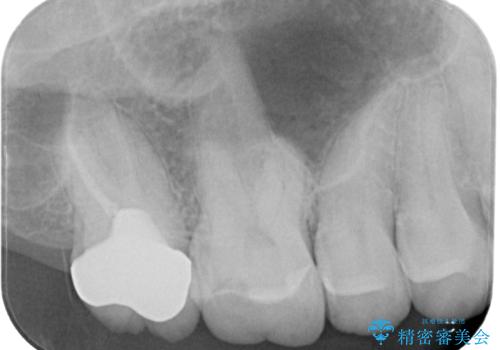

- 奥歯の被せものが欠けたとのことで来院された患者様です。上の奥歯なので機能面や強度を優先しPGAクラウン(ゴールドクラウン)のご提案をしましたが、セラミックの被せものがよいとのことでオールセラミッククラウンによる補綴治療を行っていくことにしました。

拡大鏡視野下で古い被せものを除去し、オールセラミッククラウンに適した形に整えました。

歯と歯茎の間に圧排糸と言われる糸を入れてシリコーン印象材にて型どりをしました。

患者様のご希望により、根管治療、土台のやり替えは行っていません。

患者さまにはオールセラミッククラウンの色味、機能面共に満足していただけました。

今後はナイトガードを使用してもらいながら、メインテナンスで通っていただく予定です